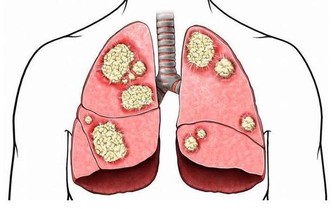

紋身過程不衛生,不規範,會增大感染乙肝、艾滋病、細菌性紅眼病和沙眼、梅毒、結核病等的風險。

韓國市面上流通的25種半永久化妝染料產品中(紋眉、紋眼線),12種產品的重金屬含量不同程度超標,部分產品的重金屬含量甚至超過標準值的30倍,其中2種產品的鎘含量和砷含量分別超標3倍、5倍,而鎘和砷已被劃分為一級致癌物。

而色素中如果含有重金屬,則有一定的致癌風險。